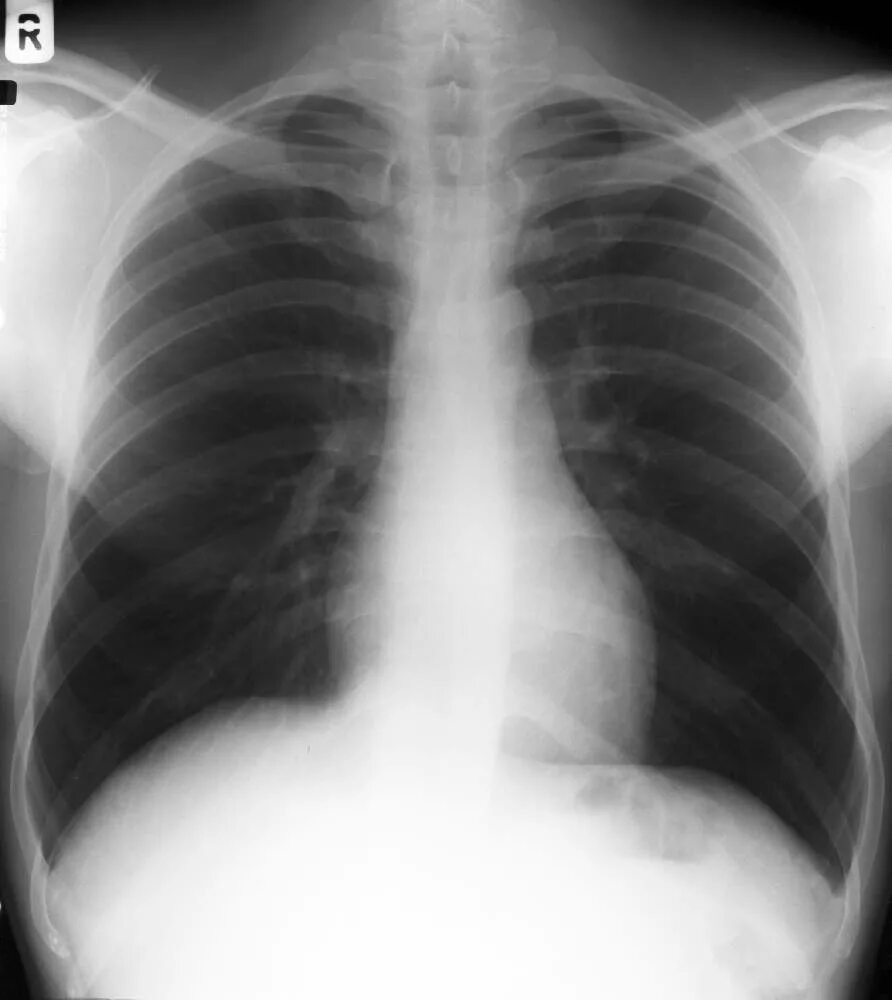

Снимок в прямой проекции